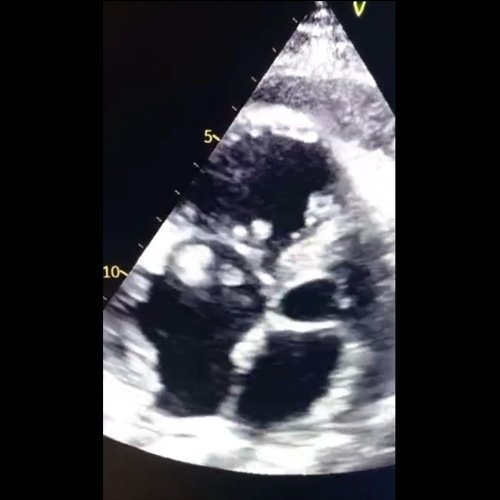

Anexo 3: Ecocardiograma transtorácico DÍA 9

Además, se realizó ecocardiograma de control el día 9, donde persistía el derrame pericárdico severo asociado a engrosamiento del mismo con presencia de vegetaciones en válvulas pulmonar y tricuspídea, dilatación severa de cavidades derechas y disfunción de ventrículo homolateral. Por dicho motivo, se solicitó un angiotomografía de tórax con protocolo para tromboembolismo pulmonar confirmándose el mismo, por lo que se encuentra anticoagulada con enoxaparina.

Contextualizando a la paciente que tiene un derrame pericárdico sin impacto hemodinámico, asintomática, severo, agudo. En el estudio ecocardiográfico, inicialmente del día 2 hacia el día 9, cambia de características, siendo informado como marcadamente engrosado, con fibrina, impresiona contenido denso. Se realiza pericardiocentesis con material macroscópicamente purulento. A su vez, se visualizan múltiples vegetaciones en válvula tricúspide y pulmonar. Por lo que interpretamos que la paciente tiene el diagnóstico de una endocarditis infecciosa (EI).